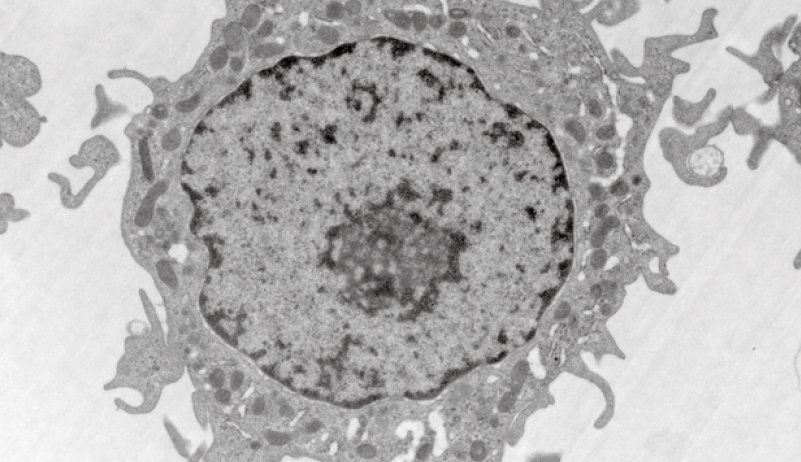

マクロファージなどの培養細胞を使ってCNFの吸入影響を評価する。